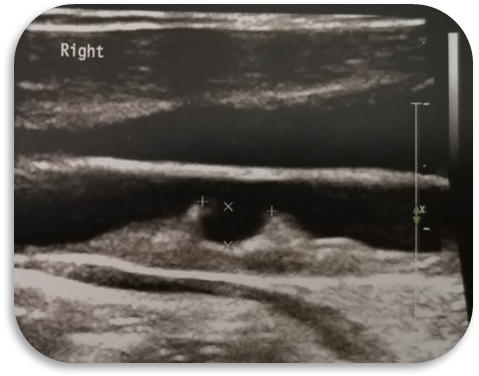

颈动脉超声在超声科检查,可以发现各种颈动脉疾病,比如:动脉粥样硬化、大动脉炎、颈动脉蹼、颈动脉夹层、纤维肌发育不良等,常见的是颈动脉粥样硬化,可以给出斑块部位大小、形态、回声等信息,评估斑块易损性、颈动脉狭窄、闭塞程度。